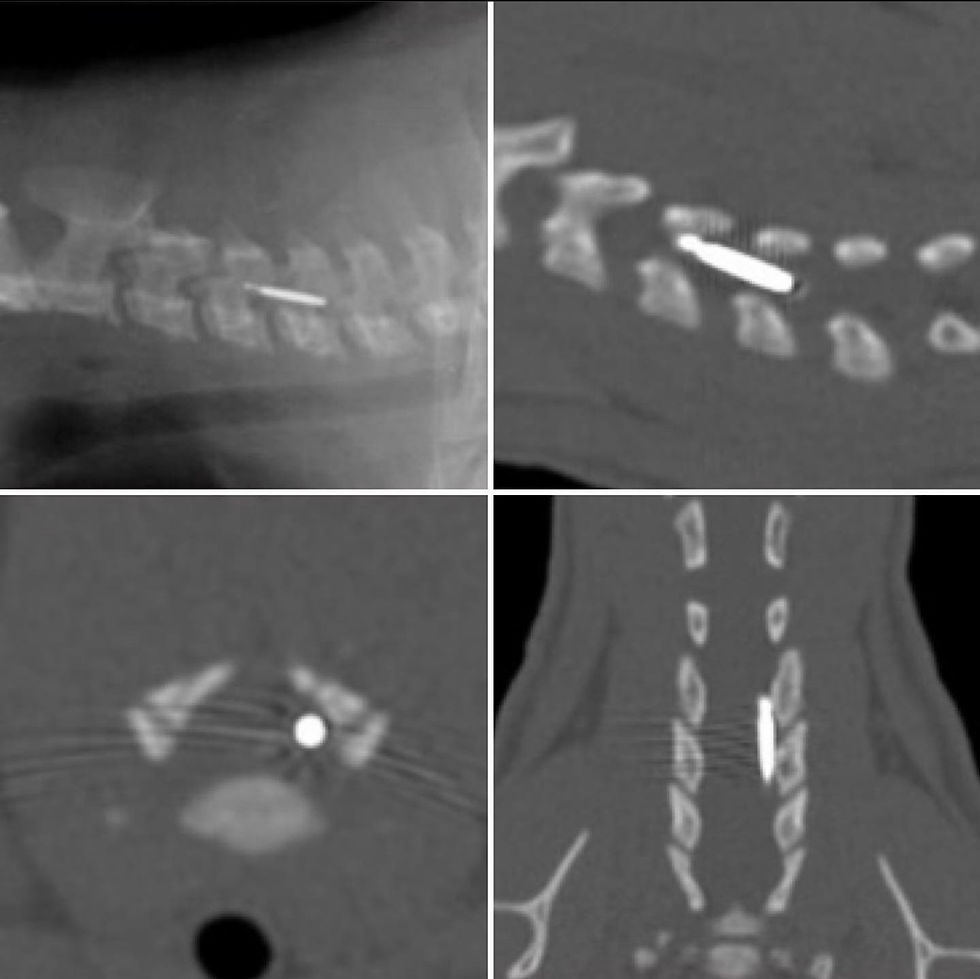

Eu não me lembro de nenhum paciente que tenha sido encaminhado para a tomografia por suspeita de corpo estranho e arrisco dizer que a maioria dos corpos estranhos observados nas tomografias tenham sido encontrados como achados de exame (mas posso estar errado já que não participo de nenhuma rotina de tomografia). Para encerrar nosso post, compartilho outra uma imagem divulgada no Instagram pelo perfil @simakov.vet onde é possível observar um microchip no canal medular de C4 e C5, em um gato Siberiano, atendido na Finlândia. Este é um corpo estranho introduzido de forma iatrogênica.